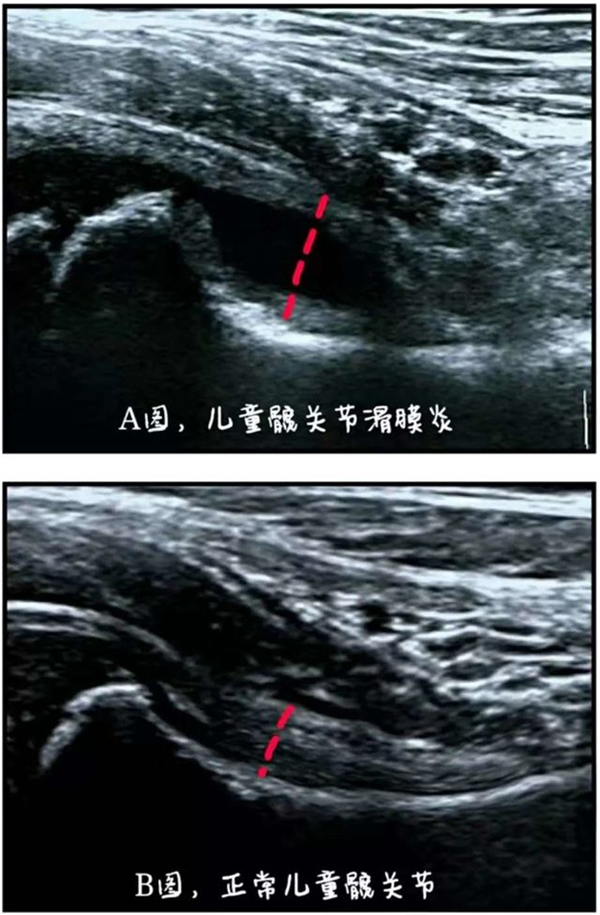

分享案例:门诊接诊一位6岁的小男孩,在前一天还挺好的,走路蹦蹦跳跳的,早上起来突然感到腿疼,不敢活动,不敢下地,下地后腿弯着使不上力,并且走路一撅一拐的,家长们急得团团转,不知道宝宝到底是真腿疼还是假腿疼。来医院彩超检查提示为髋关节一过性滑膜炎。

髋关节一过性滑膜炎是儿童时期常见的一种关节疼痛。好发于3—8岁的儿童,男孩相对多一点,具体发病原因目前不十分清楚,该病的特点是一种可以自愈的非特异性炎症。这种患儿常在发病前1~2周有上呼吸道感染史,或者白天剧烈运动后出现,通常急性起病,临床表现不特异,患儿因疼痛不愿站立,行走困难,甚至出现跛行,患侧下肢稍长。家长要及时带小孩到医院做小儿髋关节肌骨超声检查,判断髋关节是否有积液、滑膜炎。